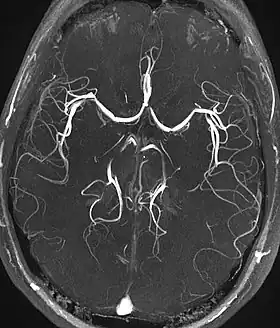

Magnetic resonance angiography (MRA) generates pictures of the arteries to evaluate them for stenosis (abnormal narrowing) or aneurysms (vessel wall dilatations, at risk of rupture). MRA is often used to evaluate the arteries of the neck and brain, the thoracic and abdominal aorta, the renal arteries, and the legs (called a "run-off"). A variety of techniques can be used to generate the pictures, such as administration of a paramagnetic contrast agent (gadolinium) or using a technique known as "flow-related enhancement" (e.g., 2D and 3D time-of-flight sequences), where most of the signal on an image is due to blood that recently moved into that plane (see also FLASH MRI).[47]

Techniques involving phase accumulation (known as phase contrast angiography) can also be used to generate flow velocity maps easily and accurately. Magnetic resonance venography (MRV) is a similar procedure that is used to image veins. In this method, the tissue is now excited inferiorly, while the signal is gathered in the plane immediately superior to the excitation plane—thus imaging the venous blood that recently moved from the excited plane.[48]

| Magnetic resonance angiography (MRA) and venography | Time-of-flight | TOF | Blood entering the imaged area is not yet magnetically saturated, giving it a much higher signal when using short echo time and flow compensation. | Detection of aneurysm, stenosis, or dissection[88] | ![]() |